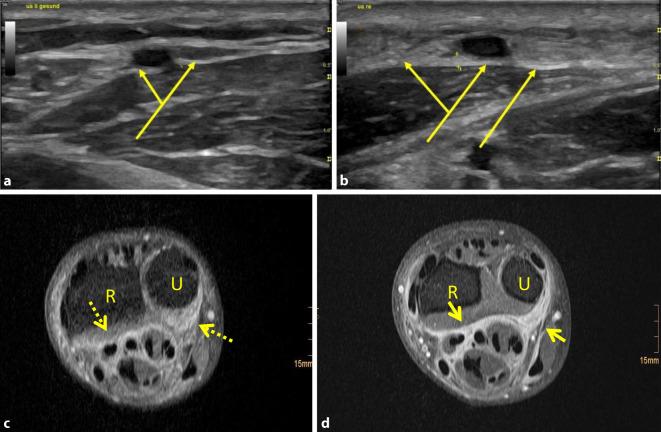

Là một bệnh hiếm gặp nhưng nguy hiểm, khiến lớp mô dưới da bị viêm → da cứng như gỗ, lâu dần gây co rút và biến dạng chi